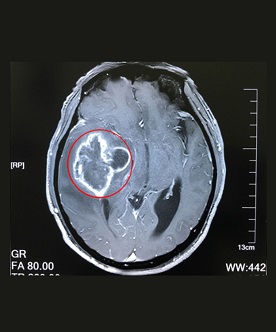

在確診腦膠質(zhì)瘤時(shí),一定要做的必然是檢查。那,腦膠質(zhì)瘤需要做哪些檢查?上海藍(lán)十字腦科醫(yī)院專家解析:膠質(zhì)瘤(gliomas)是發(fā)生...【詳細(xì)】

對(duì)膠質(zhì)瘤的治療以手術(shù)治療為主,但由于腫瘤浸潤(rùn)性生長(zhǎng),與腦組織間無明顯邊界,除早期腫瘤小且位于適當(dāng)部位者外,難以作到全部切...【詳細(xì)】